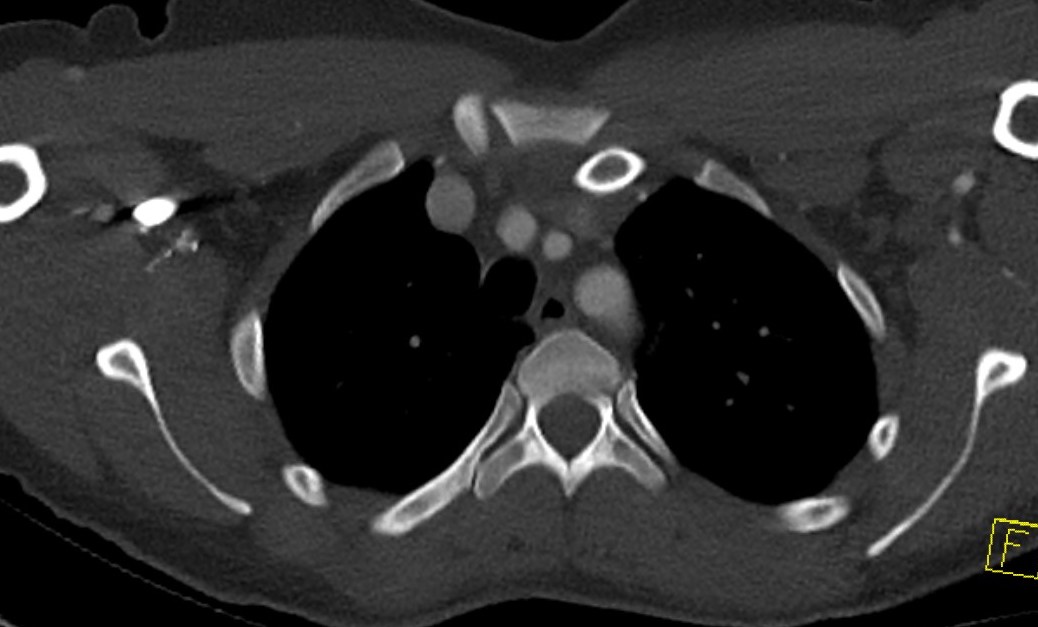

CT scan

Left posterior SCJ dislocation with pre- and post angiogram

Severe left posterior SCJ dislocation with subclavian vein compression